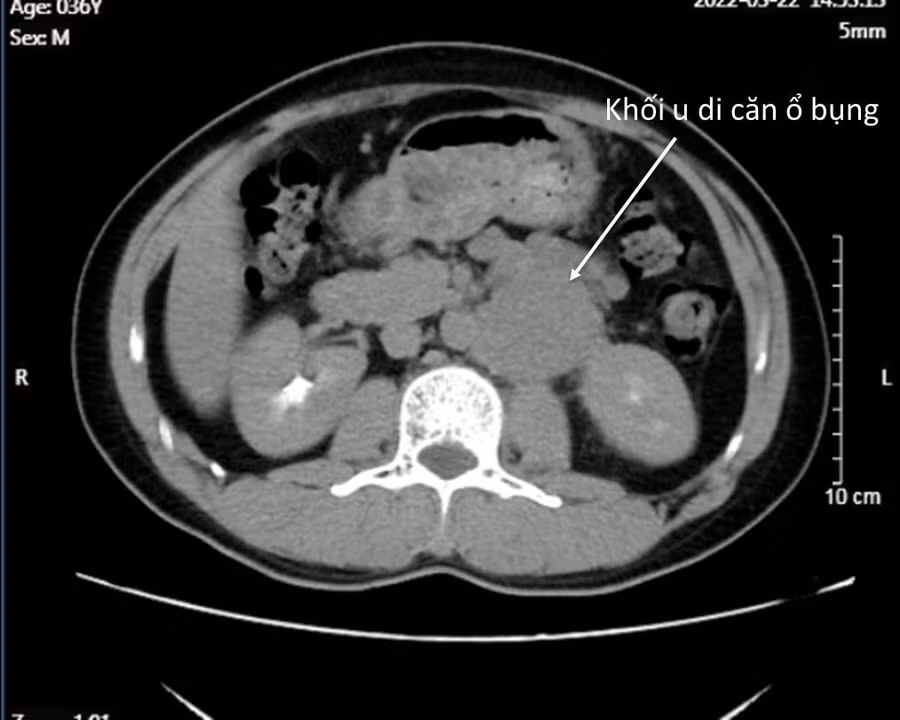

Các xét nghiệm, hình ảnh chụp cộng hưởng từ cho thấy, vị trí khối sưng vùng bẹn trái chính là tinh hoàn đã ung thư hóa, tồi tệ hơn nữa là khối u đã di căn tới nhiều vị trí vùng chậu và ổ bụng.

Hình chụp X-quang khối u tinh hoàn của bệnh nhân. Ảnh: BV.